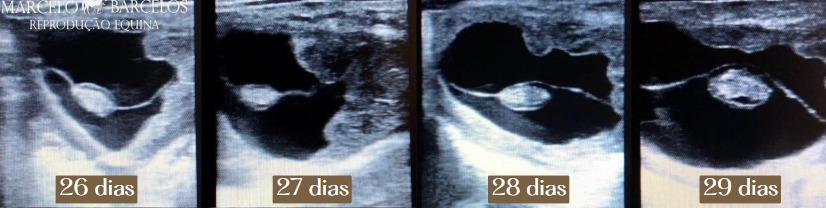

25 – 30 dias: Aparecimento do Batimento Cardíaco

Aos 25 dias, o embrião já pode ser identificado dentro da vesícula e torna-se possível detectar a atividade cardíaca do embrião, sendo um dos principais indicadores de viabilidade gestacional.

Aos 30 dias, o embrião atinge 6-7 mm, a estrutura embrionária fica mais definida, começando a desenvolver estruturas primordiais como a cabeça e os primeiros esboços de membros.